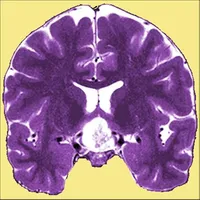

Neuro Toolkit icon

Neuro Toolkit

NEURO TOOLKIT Written by a vascular neurologist! Lots of Commonly Used Neurology/Neurosurgery Grading Scales in One Place - Many With Prognosis! NIH Stroke Scale and Much, Much More! Not Flashy - Just Fast and Functional iPhone/iPod Touch/iPad Universal App Includes: Strokes/TIAs: NIH Strok